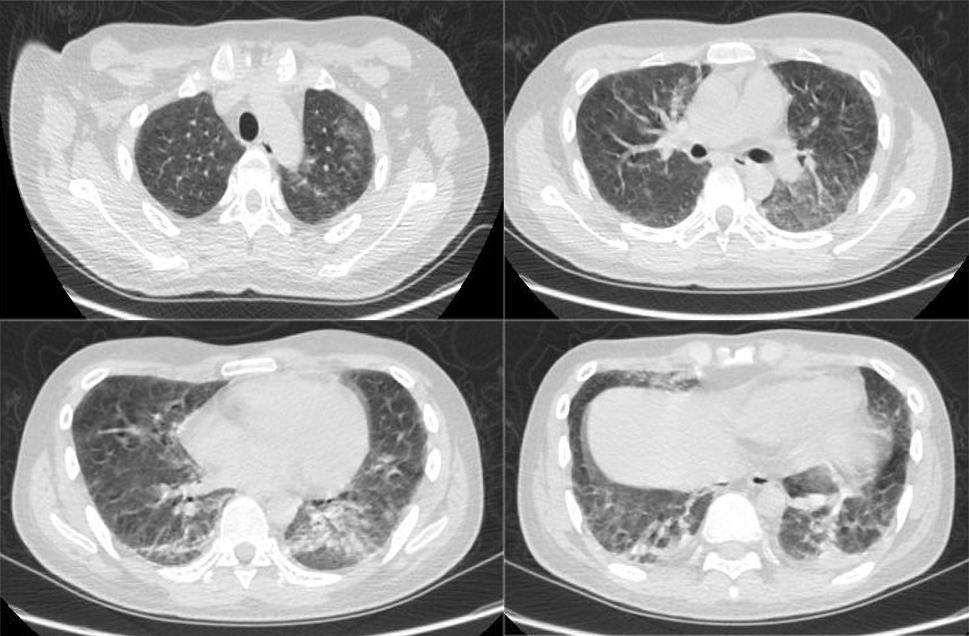

2020-12-08胸部CT

临床病例(一):池某某,男,17岁,2020年12月9日因「反复发热10天,伴气喘1天」入院。最高体温39.5℃,伴乏力,无畏冷、寒战,无咳嗽、咳痰,自行口服「退热药」后,体温降至正常。入院前1天再次出现发热,最高体温39.0℃,伴气喘,就诊我院急诊。

既往史及个人史:2020-8在肾内科诊断IgA肾病、原发性肾病综合征(系膜增生),后规律服用「甲泼尼龙、他克莫司」抗排斥。

查体:体温:36.6℃,脉搏:117次/分,呼吸:40次/分,血压:128/89mmHg。双肺呼吸音粗,未闻及干湿性啰音和胸膜摩擦音。心腹查体未见明显异常。

血气分析:pH值7.490↑、二氧化碳分压36.9mmHg、氧分压63.8mmHg↓、实际碳酸氢根27.9mmol/L↑、标准碳酸氢根28.6mmol/L↑、总二氧化碳64.9mmol/L↑、实际剩余碱4.8mmol/L↑、标准剩余碱4.5mmol/L↑、氧饱和度91.5%↓。

血常规:白细胞计数15.83*10^9/L↑、粒细胞百分比88.4%↑、粒细胞计数14.00*10^9/L↑。

CRP:85.9mg/L↑

PCT正常

呼吸道病原体谱抗体,肺炎支原体血清学,T-SPOT,术前四项均未见异常。

诊治经过如下:

患者既往有肾脏基础疾病,使用激素及免疫*制剂抑**4个月,此次肺炎伴有低氧血症,胸部CT影像学表现不典型,需完善纤维支气管镜肺泡灌洗明确病原菌。

2022年12月10日的BALF-mNGS结果示:耶氏肺孢子菌。序列数181,符合免疫功能低下宿主的常见病原菌,结合患者血液学巨细胞病毒DNA结果,考虑患者为PJP合并巨细胞病毒感染,给予SMZ联合更昔洛韦治疗,CRP和PCT明显下降。复查胸部CT较前明显吸收。

对于免疫功能抑制宿主,需积极完善病原学检查,PJP是非常常见的致病菌,当胸部CT出现间质性改变,同时伴有低氧血症,需要警惕PJP的可能,当然一部分患者可能合并有CMV的感染,需要加以鉴别。